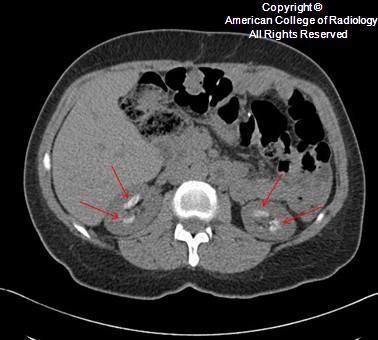

Adrenal CORTICAL carcinoma

as opposed to the medullary - pheochromocytoma